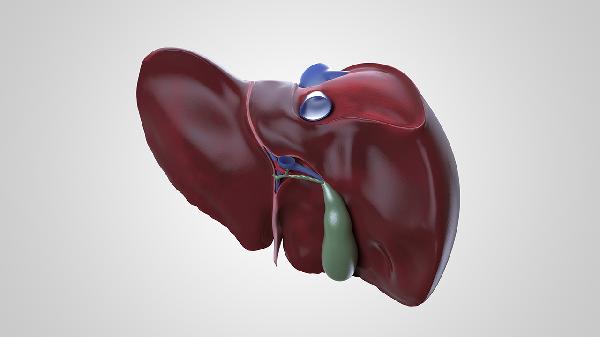

偶尔肝脏刺痛怎么办?

偶尔考虑肝痛是由肝炎或肝硬化引起的,患者需要在医生的指导下使用药物来缓解。

1、肝炎:

肝炎通常是由病毒感染、高能量饮食等原因引起的。患者患病后会出现恶心、食欲不振等症状。有些患者偶尔会出现肝脏刺痛。患者可以在医生的指导下使用药物。常见的药物有利于巴韦林胶囊、拉米夫定片等。

2、肝硬化:

肝硬化是由大量饮酒、寄生虫感染等原因引起的。患者患病后会出现腹部不适、乏力等症状,有的患者偶尔会出现肝脏刺痛的症状。患者需要在医生的指导下用药。常见的药物有螺内酯片、呋塞米片等。